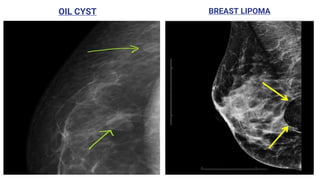

● Fat-containing lesions such as oil cysts, lipomas, galactoceles and mixed-density

OIL CYST BREAST LIPOMA

BIRADS 2 Benign Finding:Like BI-RADS 1, this is a normal assessment, but here, the interpreter chooses to describe a benign finding in the mammography report, like: ● Involuting, calcified fibroadenomas ● Multiple large, rod-like calcifications ● Intramammary lymph nodes ● Vascular calcifications ● Implants ● Architectural distortion clearly related to prior surgery. ● Fat-containing lesions such as oil cysts, lipomas, galactoceles and mixed-density hamartomas. They all have characteristically benign appearances, and may be labeled with confidence.

• #55 Oil cysts in breast imaging refer to benign breast lesions where an area of focal fat necrosis becomes walled off by fibrous tissue